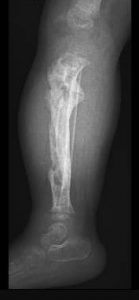

Bei der 3jährigen Chantal (Name geändert) hatten die ruandischen Kollegen einen riesigen Sequester aus der Tibia (Schienbein) entfernt. Nach Abklingen aller Infektzeichen bestand nun die Indikation den entstandenen Defekt mit einem Fibulatransplantat zu überbrücken.

Das war die Ausgangssituation.